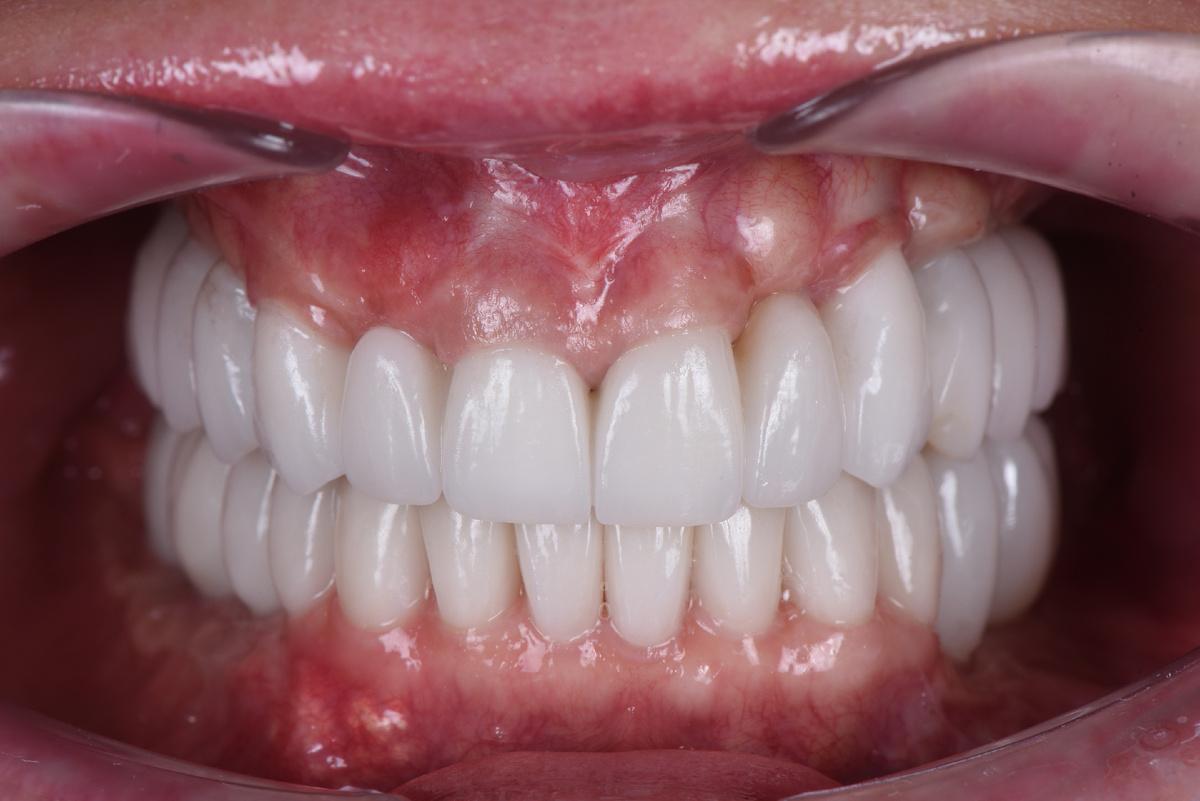

Протезирование

Оставим за скобками мероприятия по изготовлению временных конструкций, служивших не более, чем небольшим утешением нашей героине. Основная работа началась после имплантация зубов верхней челюсти, по традиции, с моделирования будущей улыбки на экране монитора (DSD)

Первая примерка :

Верхняя челюсть: 2 мостовидных протеза в жевательных отделах с опорой на 3 имплантата и мост на 6 единиц с опорой на 4 собственных зуба

Следующий шаг — коронки на нижние зубы:

Завершающий этап — после протезирования на имплантатах на нижней челюсти слева, в той области, где костная ткань восстанавливалась дольше всего